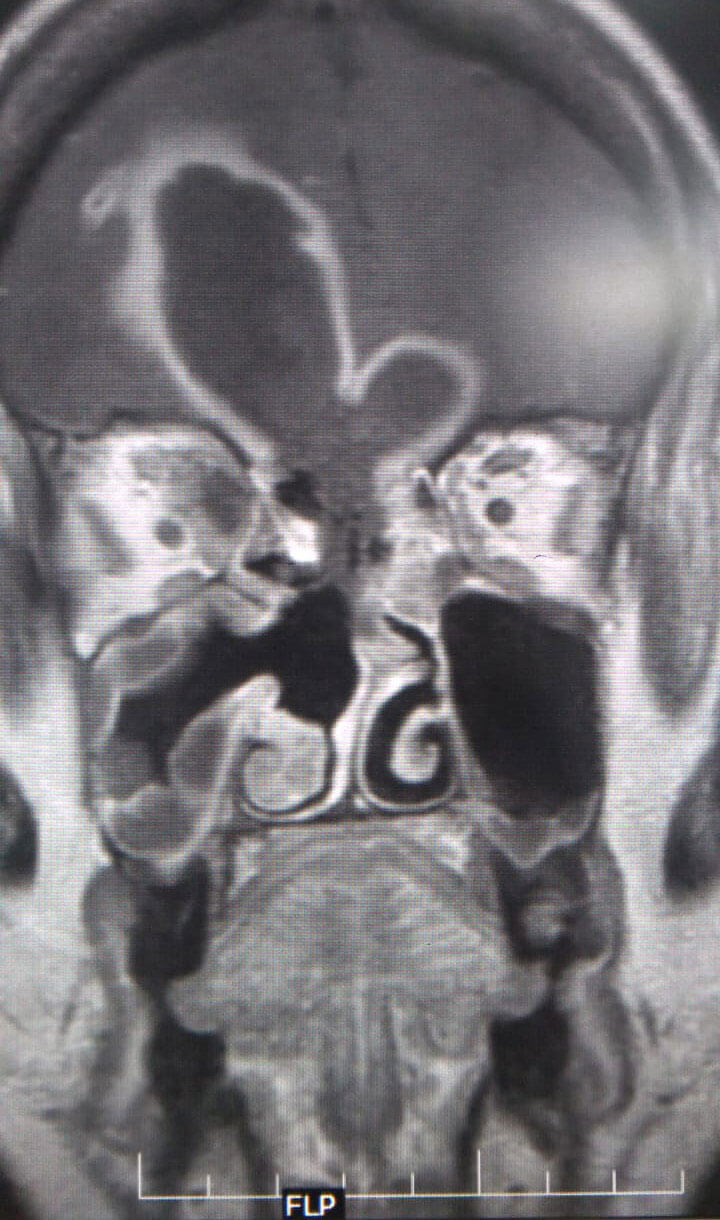

MRI scans of a patient with ROCM showing a large frontal lobe brain abscess

with necrosis of the cribriform plate (coronal and sagittal views).

The initial phase saw late presentations including cerebral mucormycosis. But overall, cerebral involvement is about 5-8%. Also, 2-3% of other patients progress to intracranial involvement in spite of aggressive treatment. Cerebritis is managed conservatively with significantly higher doses of amphotericin B. Focal abscesses have been drained by neurosurgeons. About 20% of patients have had some degree of orbital involvement. Surgical management may range from orbital decompression to selective periorbital endoscopic debridement to orbital exenteration (guided by clinical and radiological findings). Most decisions are tailored to the context.

ENT/oral/neurological/ophthalmic examinations, video nasal endoscopy, KOH mount of tissue plug (not swab), MRI brain with orbit and PNS with contrast (fat suppressed) (with a Screening CT of PNS and face) are performed. An exhaustive but practical scoring/staging system is available from radiology that we use. The definitive specimens can be sent for special fungal stains (PAS, GMS), fungal culture and histopathological examination.